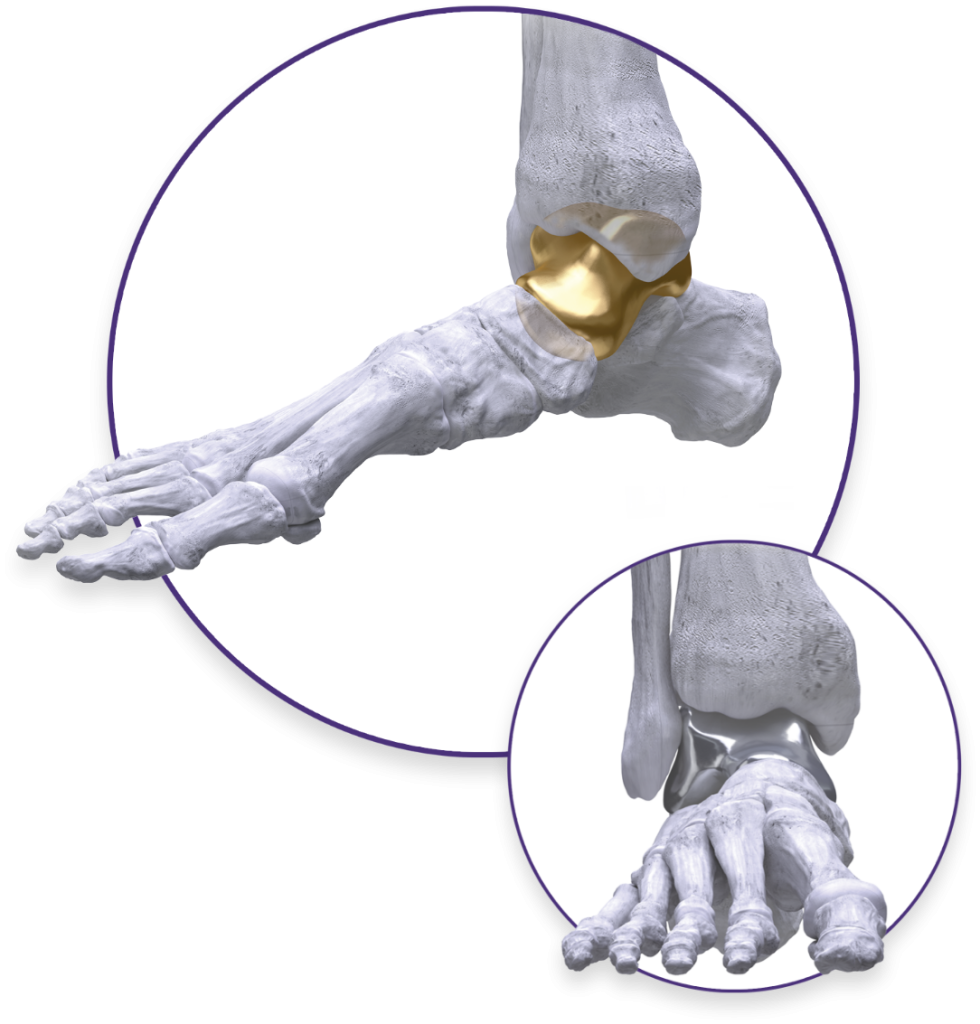

Total Talus Replacement

The Paragon 28 Patient Specific Talus Spacer is an alternative treatment option to fusion and amputation, and requires talus replacement surgery. During this procedure the native talus bone is removed and replaced with a 3D printed replica. This is considered a joint-sparing procedure, as it allows the patient to maintain motion of his/her ankle joint.

The Paragon 28 Patient Specific Talus Spacer is an additively manufactured, or 3D printed, patient specific implant that is designed and made individually for each patient using CT image data.

Total Talus Replacement

An alternative treatment option to fusion and amputation, the Paragon 28 Patient Specific Talus Spacer is indicated for avascular necrosis of the ankle and requires total talus replacement surgery.

The procedure is designed to relieve pain and preserve motion in the ankle joint by replacing the patient’s damaged talus with a 3D printed replica of his/her bone. Talus replacement surgery is considered a joint sparing procedure as it allows the patient to retain motion in the ankle joint.